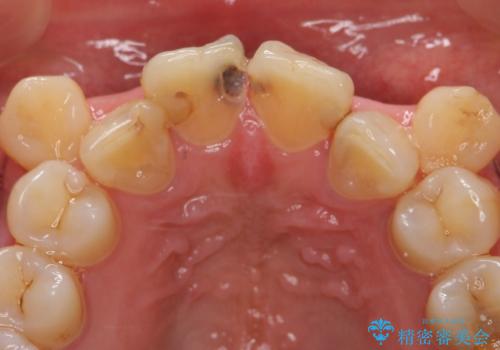

- 上顎前歯の見た目が気になるのでセラミックにしたいといらっしゃった方の症例です。

右上2は歯の神経が死んでおり、根尖病変を認めたため根管治療を行いました。

その後右上1,2番目及び左上1番目の歯に対してオールセラミッククラウンによる補綴を行いました。